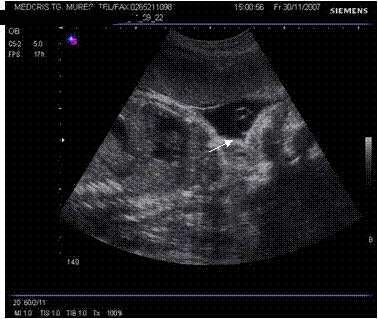

Fig. nr.217. Placenta praevia centrala la 15 saptamani ( linia indica raportul placenta praevia cu orificiul cervical intern)

Fig. nr.218. Placenta praevia complet centrala , la aceeasi sarcina ca in figura precedenta, dar la 28 saptamani gestationale

Fig. nr.219. Placenta praevia marginala , la nivelul orificiului cervical intern marcat cu linie, se observa marginea inferioara a placentei, inserata pe peretele uterin anterior